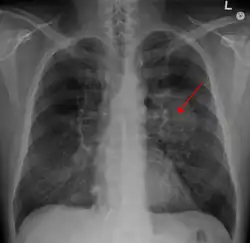

Klasický rentgenový snímek hrudníku vykazující karcinom plic (označen šipkou) | |

Provedení rentgenu hrudníku je jedním z prvních kroků při vyšetření osoby trpící symptomy, jež by mohly naznačovat karcinom plic. Může odhalit přítomnost tumoru, rozšíření mezihrudí (naznačující, že tumor napadl lymfatické uzliny), atelektázu (kolaps), konsolidaci plic (pneumonii) nebo fluidothorax.[5] Ke zjištění detailnějších informací o typu a rozsahu onemocnění se typicky používá CT snímkování. Bronchoskopie nebo CT snímkováním řízená biopsie často slouží k odebrání vzorku tumoru pro účely histopatologie.[13]

Rakovina plic se na rentgenu hrudníku často objevuje jako solitární plicní uzel. Diferenciální diagnostika však uvádí řadu dalších onemocnění s podobným symptomem. Stejný příznak může způsobit i tuberkulóza, plísňové infekce, metastatická rakovina nebo organizující se pneumonie. Mezi méně běžné příčiny solitárního plicního uzlu patří hamartomy, bronchogenní cysty, adenomy, arteriovenózní malformace, plicní sekvestrace, revmatoidní uzlíky, Wegenerova granulomatóza nebo lymfom.[57] Karcinom plic může být odhalen i náhodně jako solitární plicní uzel na rentgenovém nebo CT snímku hrudníku pořízeném pro jiný, nesouvisející účel.[58] Definitivní diagnóza karcinomu plic se stanovuje na základě histologického vyšetření podezřelé tkáně z hlediska klinického a radiologického.[1]